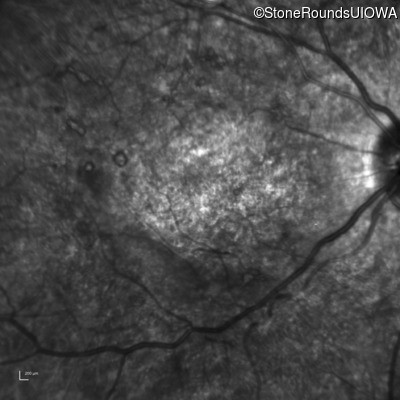

Infrared Fundus Photograph - Right - 20/400 sc

Exemplar

Infrared Fundus Photograph - Left - 20/250 sc